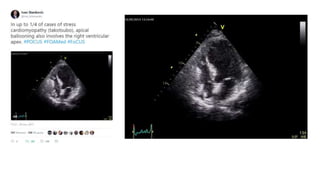

January 9th, 2015

August 6th,

2016

Circulation. 2017;136:2178–2188